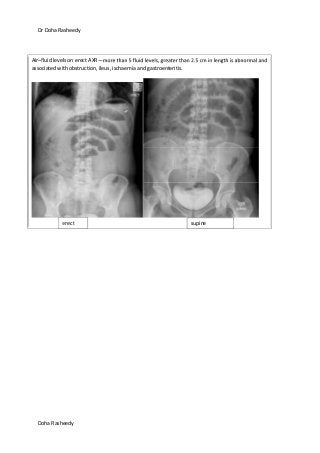

Air–fluid levels on erect AXR—

associated with obstruction, ileus, ischaemia and gastroenteritis.

erect supine